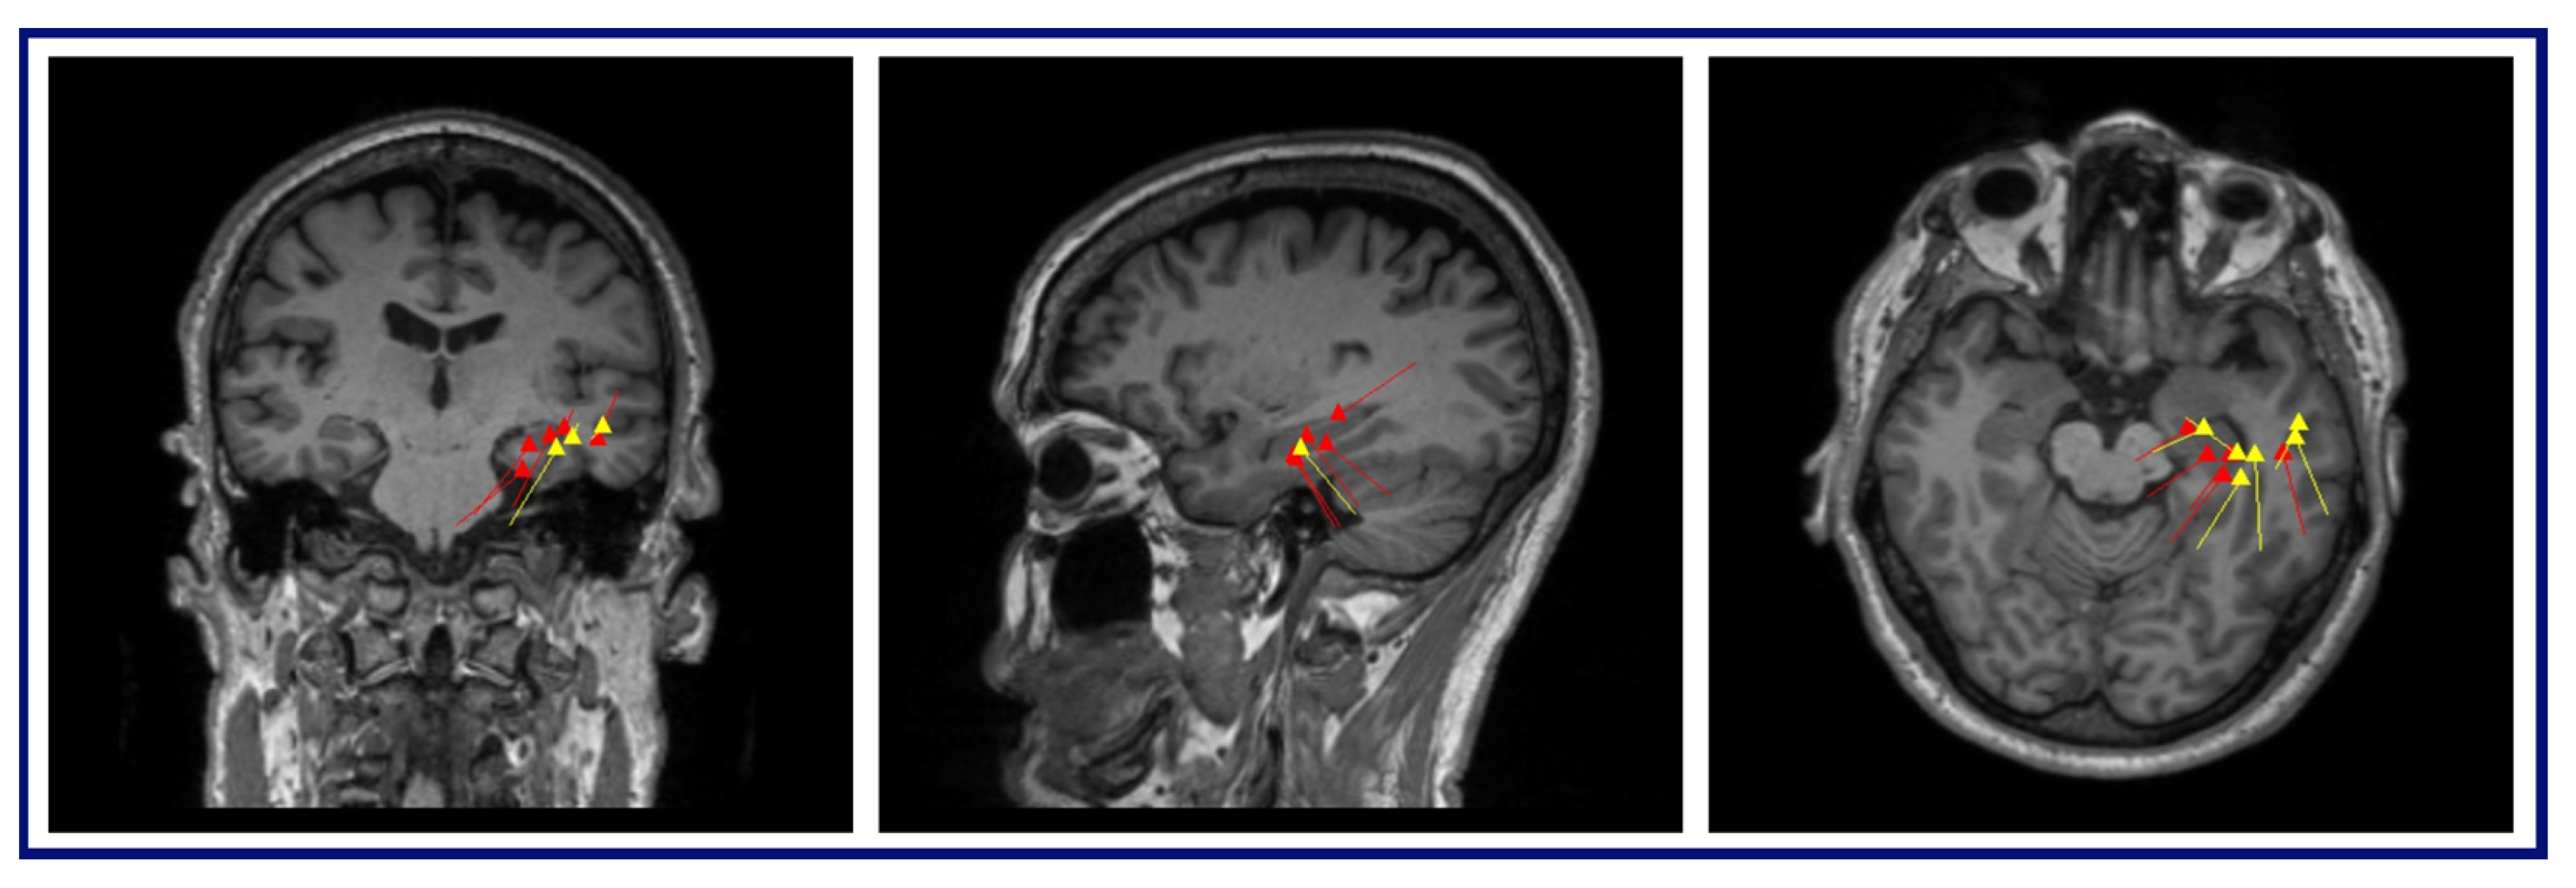

The MEG results for this patient were as follows: (A) Conventional preprocessing—A loose cluster in the left inferior and middle frontal gyri in the expected region of Broca’s area, and seven additional dipoles, which were mapped within the large artifact area in the left frontal lobe. (B) ICA-based preprocessing—Two tight clusters, one in the left inferior frontal gyrus posterior to the resection area, and one in the nearby anterior insula, with two additional dipoles within the left middle frontal gyrus, posterior to the resection (Figure 6).

Figure 6.

MEG dipole analysis: A comparison of dipole analysis between conventional and ICA-based preprocessing techniques on Patient 2. This figure also illustrates that the dipoles (represented by yellow lines and triangles) fitted with the ICA-based preprocessed data show diminished association with the RNS device artifact area and increased concordance with the hypothesized seizure onset zone (left inferior frontal gyrus and left insula) compared to the conventional preprocessing, indicating enhanced localization and reduced interference.

Dipoles fit with the ICA-based processed data demonstrated a reduced relationship with the RNS artifact area, i.e., the clusters and dipoles localizing to areas well-distinguished and further from the area of the RNS device, demonstrating less interference from the artifact. In the case of Patient 1, the conventional preprocessing showed tight clusters in the left precentral and postcentral gyri, bordering an area on the MRI showing a large artifact from the RNS device. However, with the ICA-based preprocessing, the tight cluster was found within the left inferior frontal and precentral gyri, with isolated dipoles localizing to the SMA, and bordering or within the dysplastic frontal lobe area, suggesting a more accurate localization within the clinically relevant regions of interest. Similarly, in the case of Patient 2, the conventional preprocessing showed dipoles bordering or within the large artifact area in the left frontal lobe. In contrast, the ICA-based preprocessing revealed two tight clusters in the left inferior frontal gyrus and left insula, with two additional dipoles within the left middle frontal gyrus. The results of the ICA-based processing were overlapping SOZs detected by the previous invasive study. In summary, the ICA-based preprocessing for the MEG results provided information that was more consistent with other imaging findings, clinical information, and epileptogenic zones identified by SEEG.